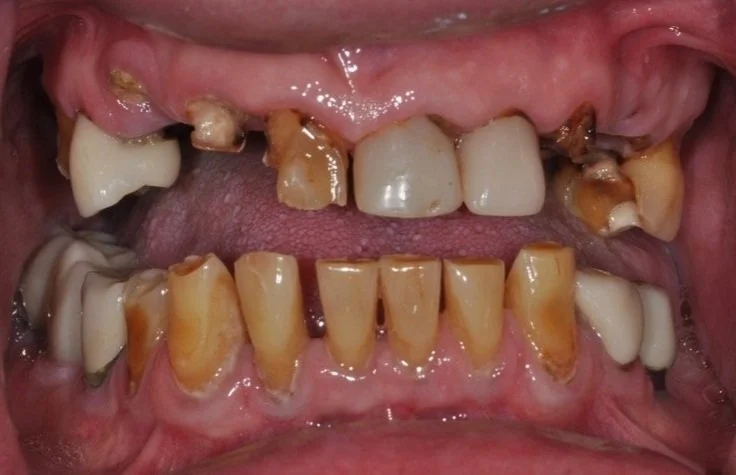

👀 Step 1: Pre-Op Evaluation

Before removing the tooth, we assessed bone health and root position with detailed imaging. In this case, the tooth had a prior root canal and a cavity on the back side, which caused the crown to loosen and eventually fall off. This tooth could not be saved by a new crown, so it needed to be extracted to prevent risk of infection and further damage of surrounding tissue. After reviewing alternative options, this patient is planning on a future dental implant to restore the site.

X Ray of tooth #18 Prior to Extraction

Photo of tooth #18 prior to extraction

✅ Purpose: understand root formation, nerve anatomy, and ensure the socket walls are intact for grafting.